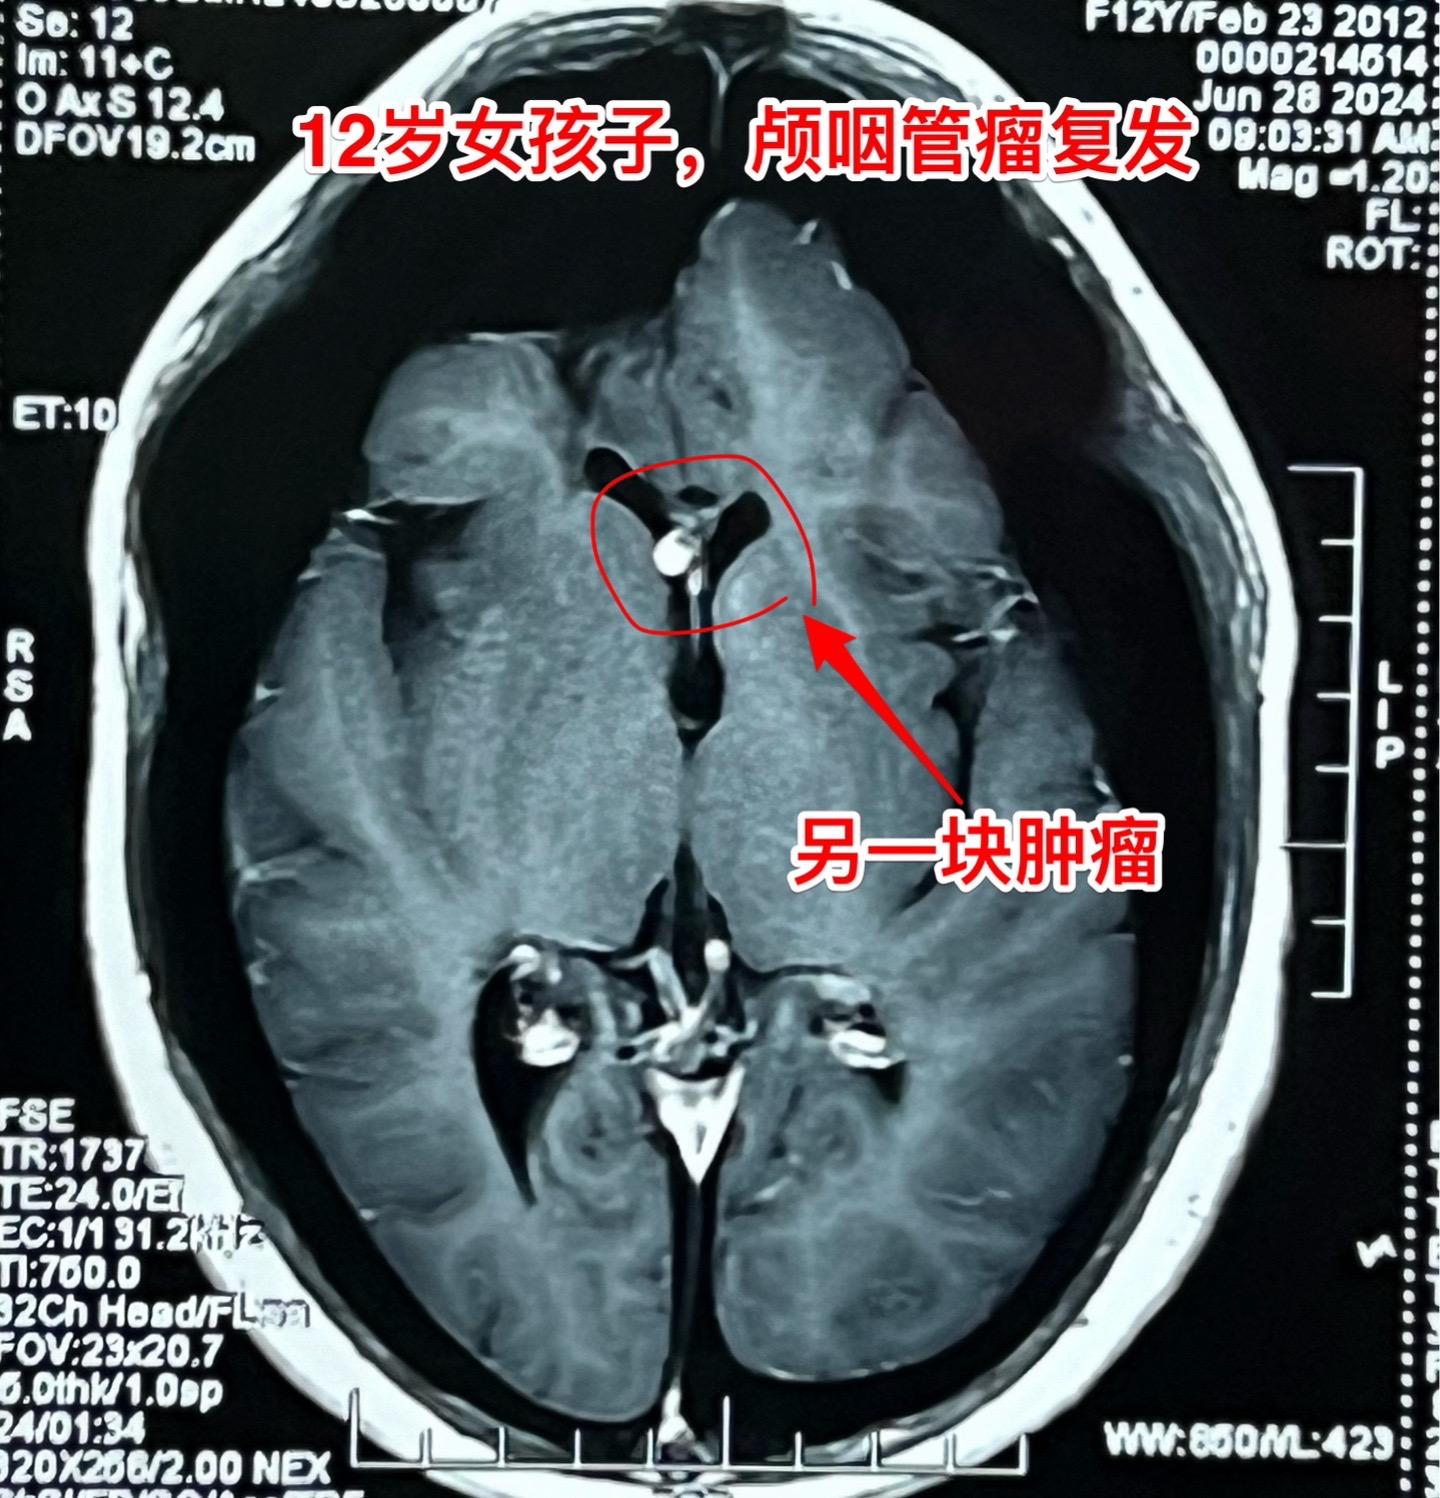

开颅手术+2次伽马刀治疗后颅咽管瘤复发。12岁的四川女孩子,5年前发现颅咽管瘤,在上海作过一次开颅手术,因颅咽管瘤残留先后作了两次伽马刀治疗。到三博脑科医院就诊时右眼已经失明了。 这样的颅咽管瘤属于难题中的难题! 肿瘤在增大,尽管切除肿瘤的难度大,我们不应该放弃,而是要积极再次手术,争取将肿瘤完全切除。 2024年7月2日作了开颅手术,将巨大肿瘤完全切除。